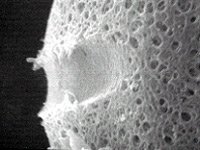

Laser Assisted Hatching

Assisted hatching is a technology which helps embryos to attach to the womb of the woman. Pregnancy cannot occur unless the human embryo hatches.

Pregnancy rates for in vitro fertilization procedures with assisted hatching have been shown in some published studies to be higher than for IVF without hatching. There is an improvement in the rate of embryo implantation and pregnancy with the use of assisted hatching.

During the cleavage of the early foetus, zona pellucida hardens. This development is normal and the purpose is to keep the cells in the egg together. Removing the egg for in vitro fertilization and micro insemination takes it out of its natural environment. This procedure tends to lead to egg shells that harden faster those of normally fertilized eggs.

Especially women older than 37 years of age, have a tendency to produce eggs with a harder zona pellucida than younger women. The same goes for women with a high level of follicle stimulating hormone (FSH). This can be diagnosed from a blood sample. Especially women older than 37 years of age, have a tendency to produce eggs with a harder zona pellucida than younger women. The same goes for women with a high level of follicle stimulating hormone (FSH). This can be diagnosed from a blood sample.

The problem of a harder zona pellucida is that the egg may not hatch and thus not attach to the woman’s womb. Hatching of the egg is necessary to become pregnant. We know that eggs from older women have problems hatching, explaining why some older women have problems becoming pregnant.

Laser assisted hatching is one out of several methods to help the fertilized egg hatch and attach to the womb. Other methods are acid or mechanical hatching of one a part of zona pellucida. Laser assisted hatching is a gentle and safe way to weaken a part of zona pellucida. After treating the fertilized egg with laser assisted hatching, we transfer the embryo into the woman’s womb. In most cases the embryo will attach for normal growth and development.